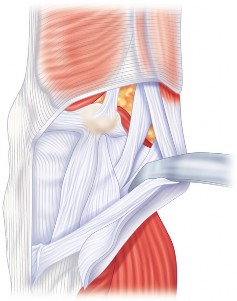

هذه الجراحة ليست مجرد استبدال للمفصل التالف، بل هي عملية تصحيحية شاملة تهدف إلى إعادة المحاذاة الطبيعية للركبة والتخلص من الانحراف التقوسي الذي يسبب الألم ويُسرّع من تدهور المفصل. بفضل الخبرة الواسعة للأستاذ الدكتور محمد هطيف التي تمتد لأكثر من عقدين من الزمن كأستاذ جامعي وجراح عظام متخصص، وباستخدامه لأحدث التقنيات الجراحية مثل الجراحة المجهرية وتنظير المفصل بتقنية 4K وزراعة المفاصل المتقدمة، يتمكن مرضى خشونة الركبة التقوسية في صنعاء من استعادة حركتهم الطبيعية والعيش بلا ألم.

يُعد الانحراف التقوسي مشكلة شائعة وقد يكون خلقيًا (موجودًا منذ الولادة)، ولكنه غالبًا ما يتطور بمرور الوقت نتيجة لخشونة الركبة المتقدمة، حيث يؤدي التآكل غير المتساوي للغضروف إلى تفاقم التشوه. تصحيح هذا الانحراف هو جوهر جراحة استبدال مفصل الركبة التقوسي، وهو ما يتقنه الأستاذ الدكتور محمد هطيف لضمان استقرار المفصل وطول عمره.